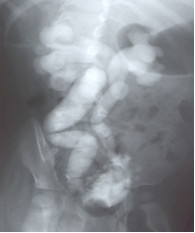

U 3-letniego dziecka stwierdzono niedorozwój kości krzyżowo-ogonowej (patrz zdjęcia poniżej). Jakie badanie powinno być wykonane w następnej kolejności?

U 2-letniej dziewczynki z nawracającymi zakażeniami układu moczowego, wykonano cystografię, której obraz jest pokazany poniżej. Jakie postępowanie powinno być wdrożone?